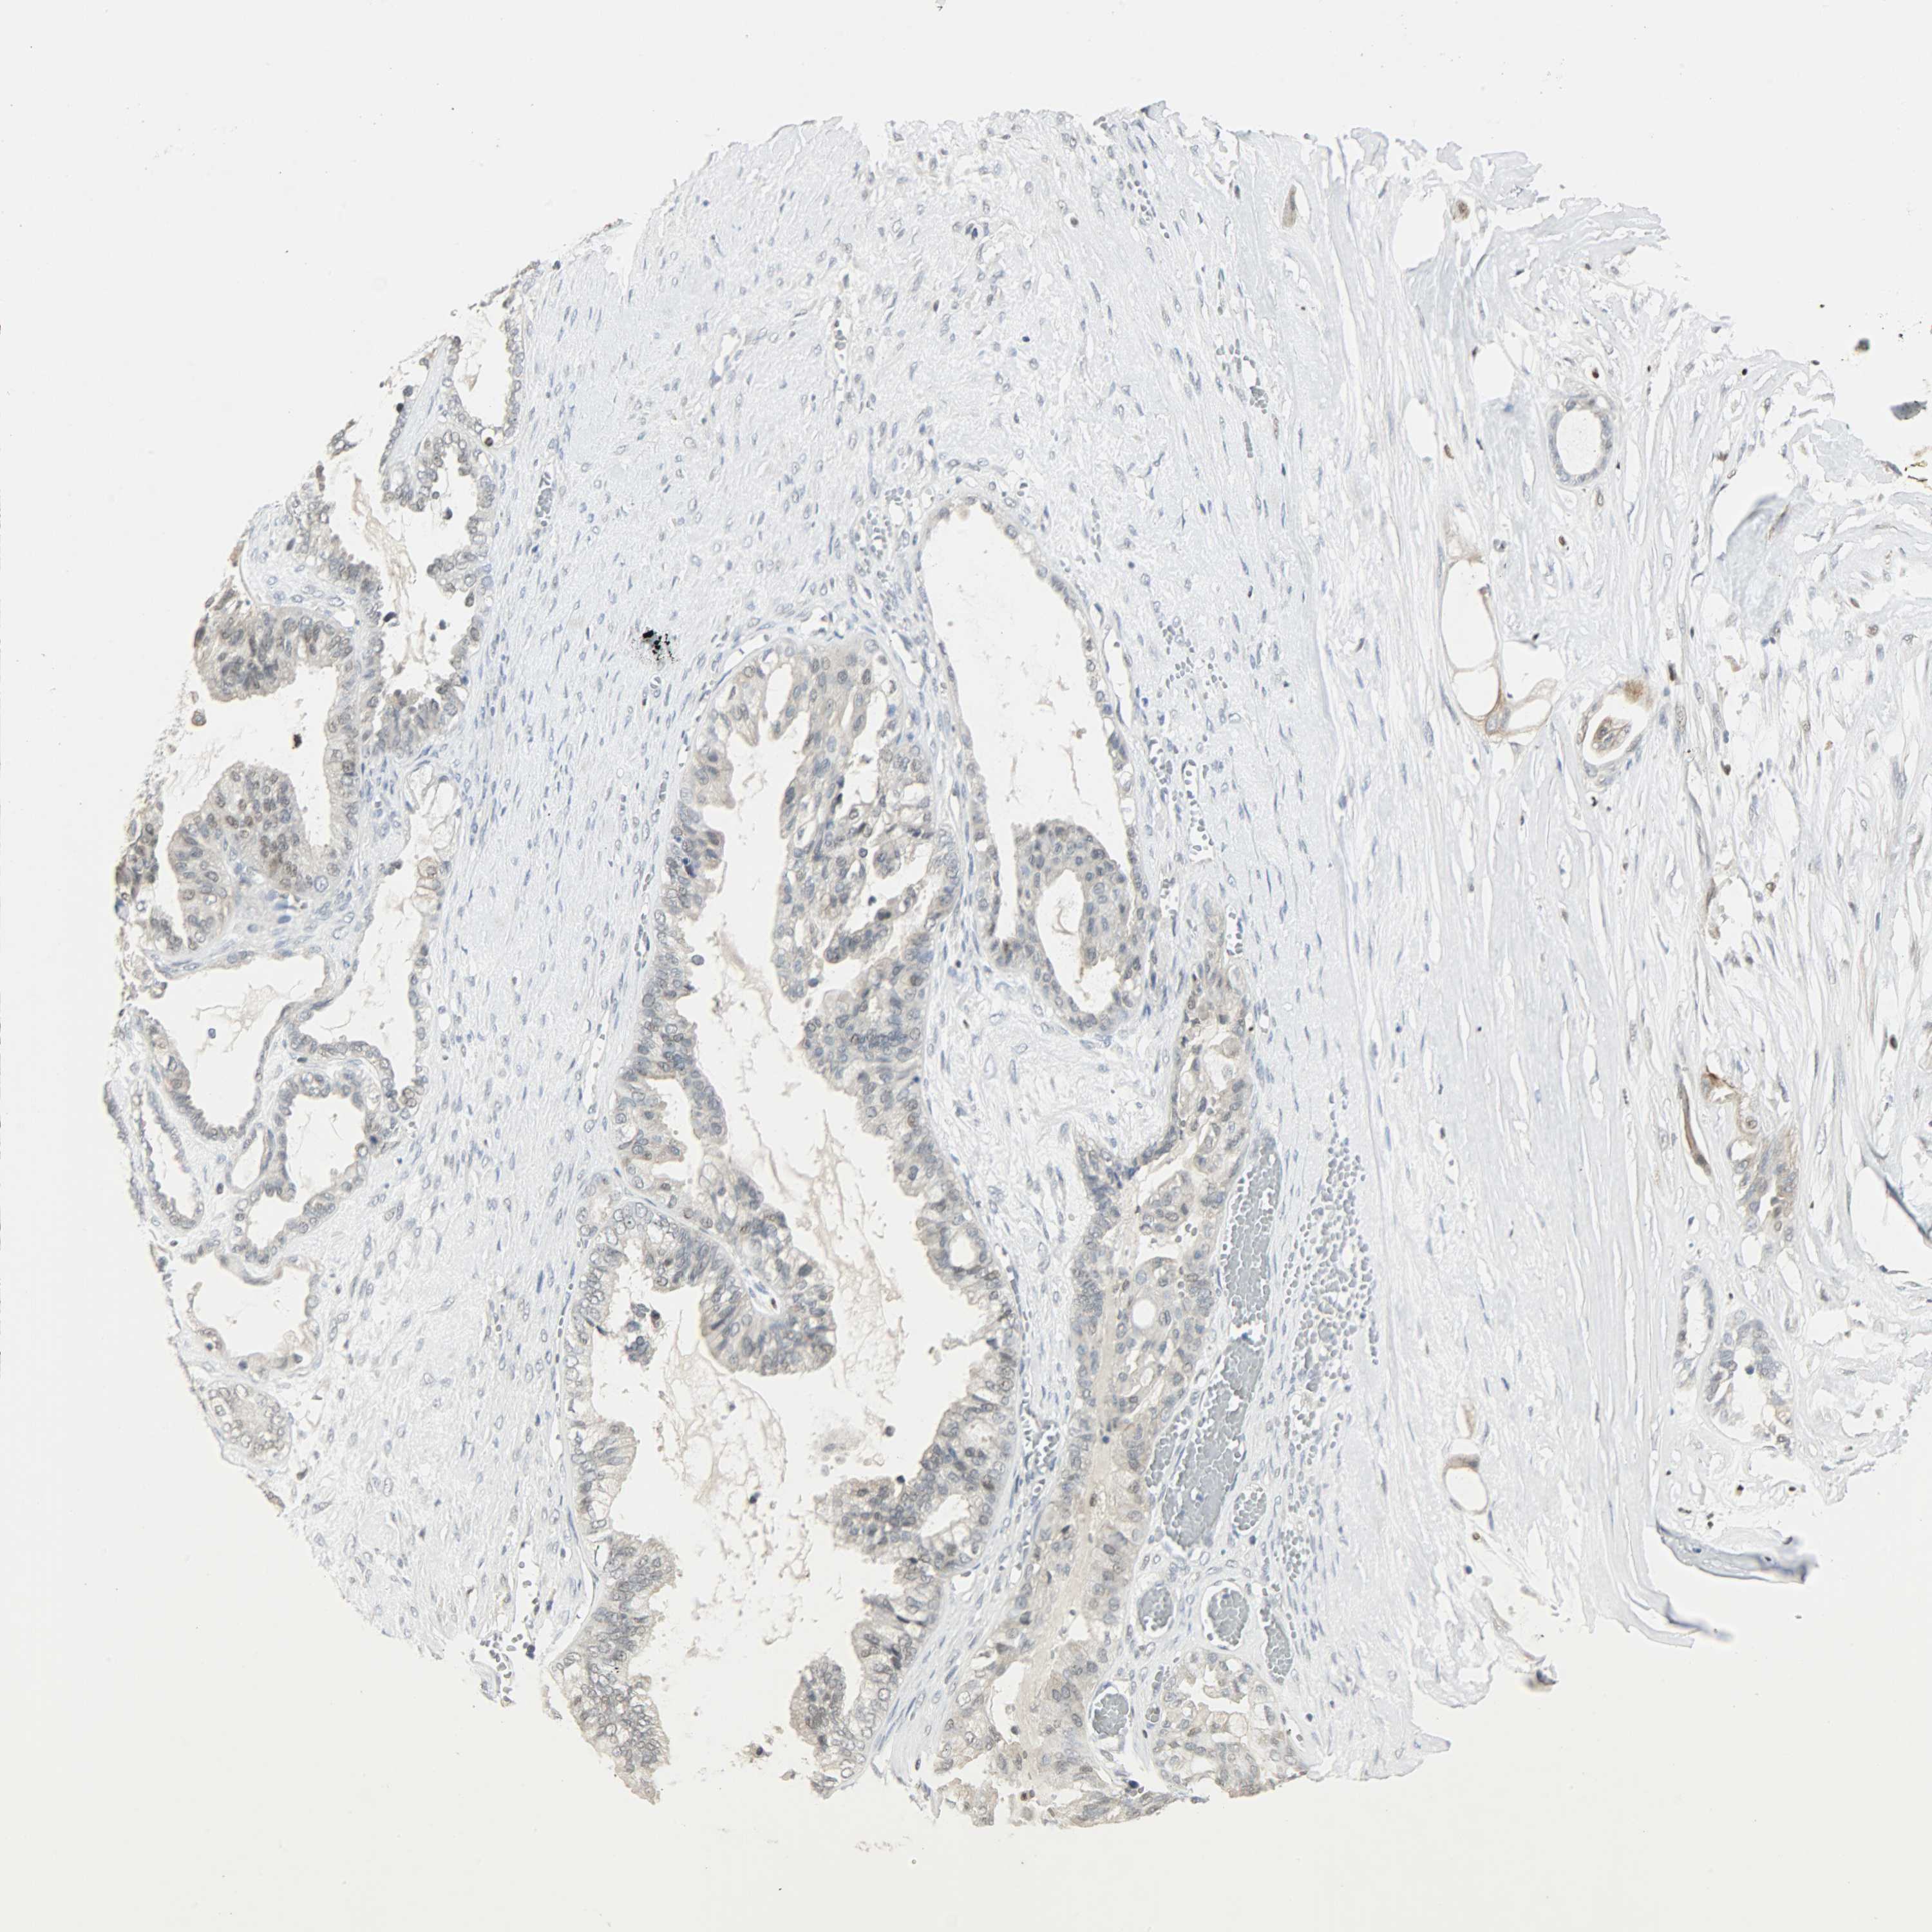

OVARIAN CANCER - Protein expressioni

A mouse-over function shows sample information and annotation data. Click on an image to view it in a full screen mode. Samples can be filtered based on level of antibody staining by selecting one or several of the following categories: high, medium, low and not detected. The assay and annotation is described here.

Note that samples used for immunohistochemistry by the Human Protein Atlas do not correspond to samples in the TCGA dataset.

Antibody stainingi

Antibody staining in the annotated cell types in the current human tissue is reported as not detected, low, medium, or high, based on conventional immunohistochemistry profiling in selected tissues. This score is based on the combination of the staining intensity and fraction of stained cells.

Each image is clickable and will lead to virtual microscopy that enables deeper exploration of all samples and also displays staining intensity scores, fraction scores and subcellular localization as well as patient and tissue information for each sample.

Antibody CAB004282

Staining

High

Medium

Low

Not detected

Intensity

Strong

Moderate

Weak

Negative

Quantity

>75%

75%-25%

<25%

None

Location

Nuclear

Cytoplasmic/membranous

Cytoplasmic/membranous,nuclear

Cystadenocarcinoma, serous, NOS

Carcinoma, endometroid

Carcinoma, NOS

Cystadenocarcinoma, mucinous, NOS